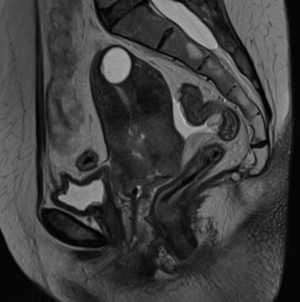

МР-диагностика рака тела матки

МР-диагностика рака шейки матки

МР-диагностика рака яичников